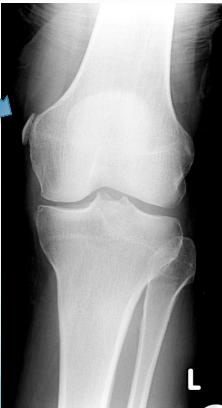

Diagnostic Studies for MCL

X-ray

- May show avulsion fracture

- Stress Film: Shows ligament laxity